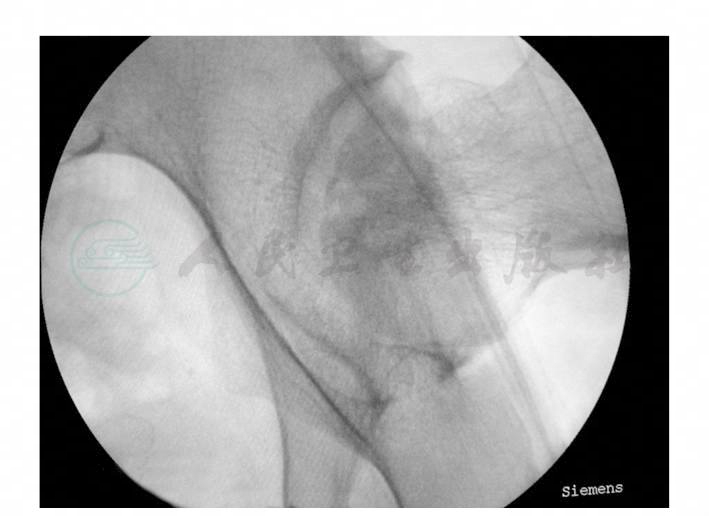

麻醉成功后患者取仰卧位,患肢以牵引床持续牵引,并于C形臂X线机透照下确定体位,取左髋外侧原切口切开,适当切开阔筋膜,由于空心钉轻度向外移位,钉尾已突出于骨皮质表面,寻找较为容易,以合适的螺丝刀轻松取出。取出后在C形臂X线机透照下再次观察股骨头坏死情况(图4)。

图4 术中透视情况

可见股骨头负重区密度不均,并伴有囊性变,位置与后上方2枚空心钉钉孔接近。遂在C形臂X线机透照监视下再次沿此2钉孔置入导针并确定位置,并沿导针置入空心套管至囊性变的股骨头负重区(图5)。